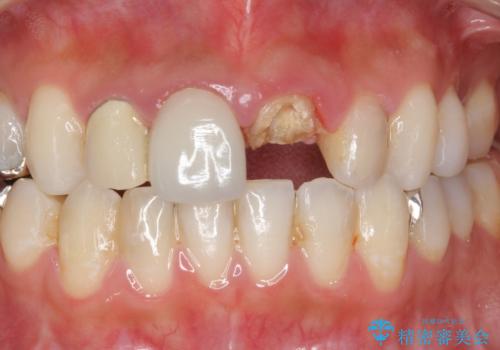

- 過去に他院で治療した前歯が取れたとの事で来院。

被せ物だけでなく中の土台まで取れていました。

歯の根っこのお掃除(根管治療(保険))を行い、土台を立ててセラミックの被せ物で治療しました。

また、隣の歯も被せ物の適合が悪く予後がよくないので根管治療(保険)を行い、セラミックの被せ物で治療を行いました。